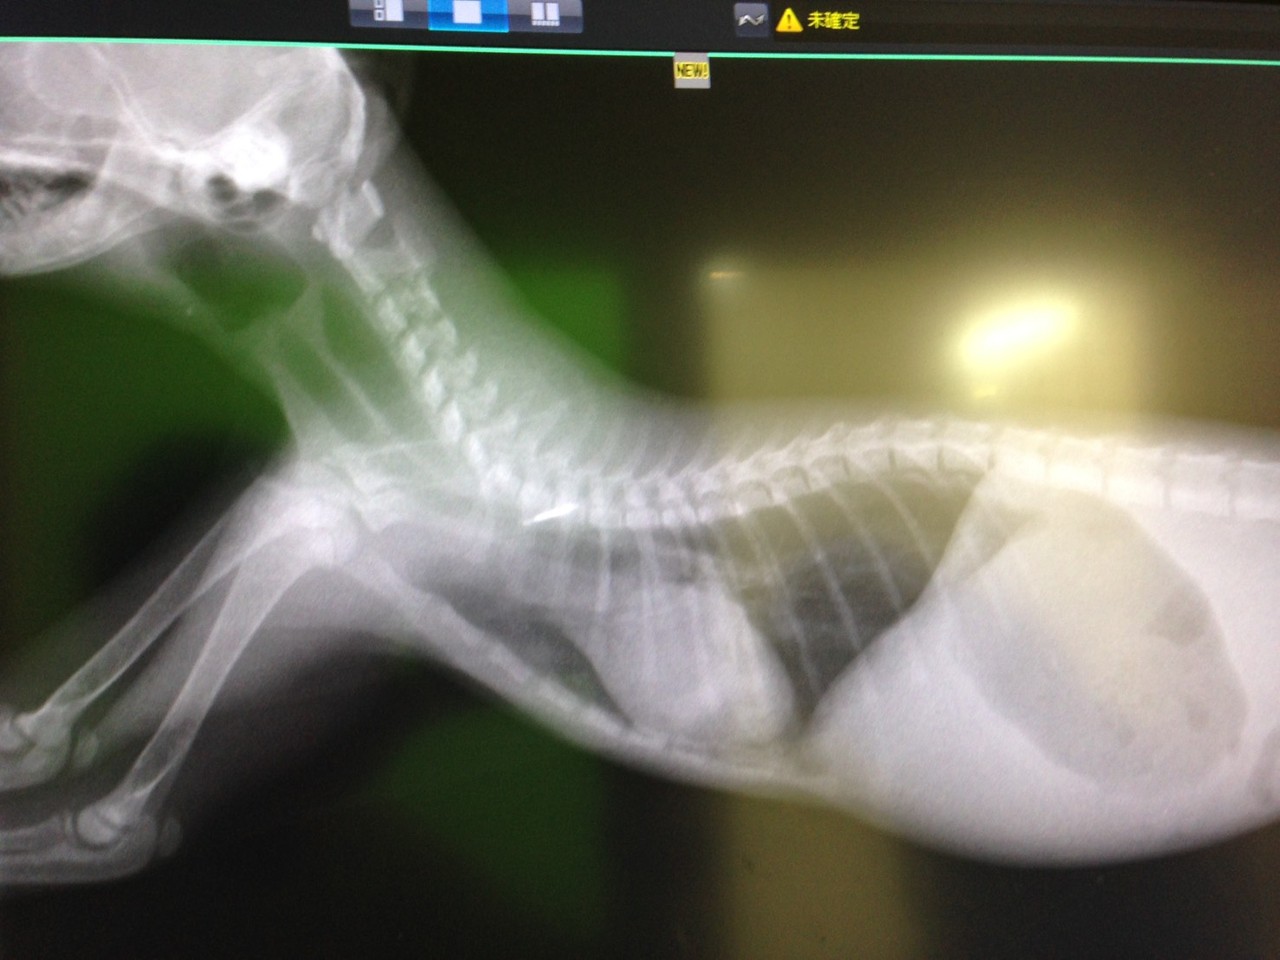

小さな 長毛の子猫は食べなくて元気がありませんでした 、

病院に連れて行ったところ 熱が40度、肺炎に掛かっているので 急遽入院になりました。